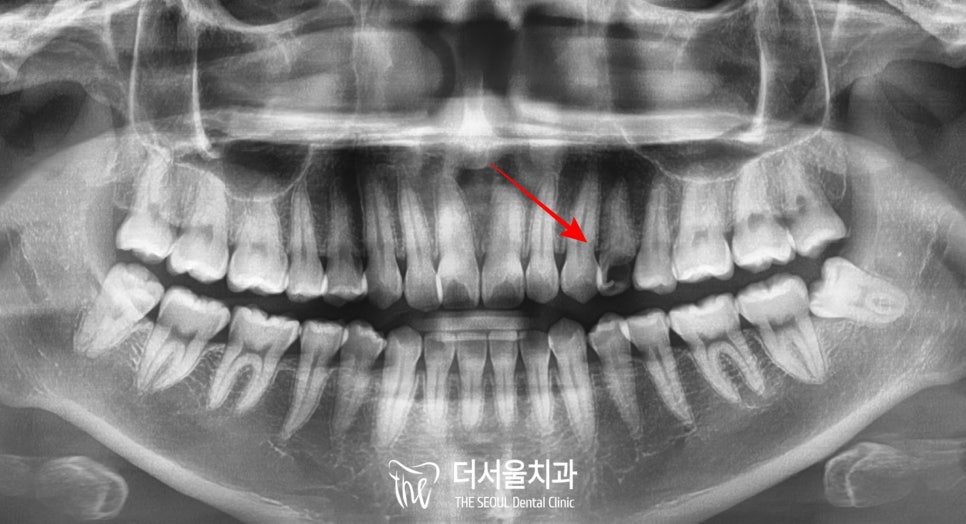

2. 진단

성남 치과 에서는

파노라마를 찍어서

조금이라도 살릴 수 있는 방안이

없을까 한번 더 살펴보았는데요,

엑스레이에서 보이는 것과 같이

한눈에 보기에도

제가 빨간색 화살표로 표시해둔 부위만

까맣게 보이죠?

그만큼 파절량이 많아

방사선이 많이 투과되고 있기 때문입니다.